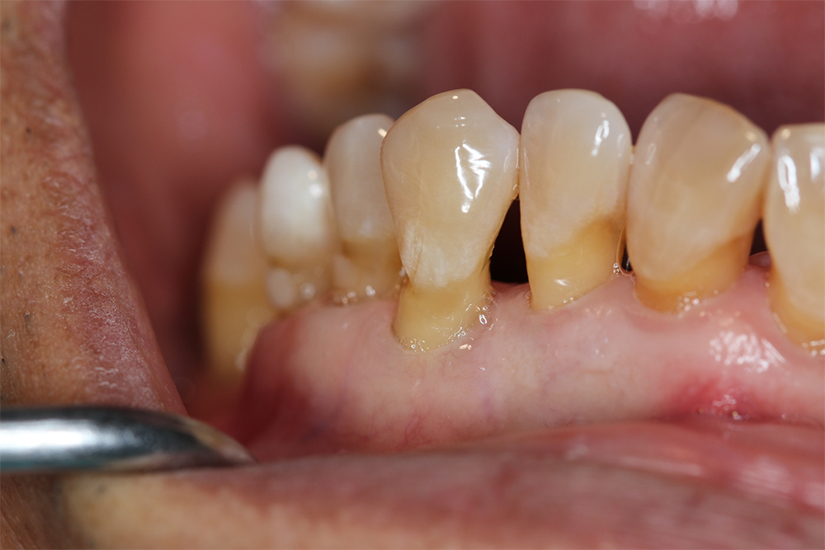

Retracția gingivală este o afecțiune orală des întâlnită la pacienții care vin în clinica dentară. Această problemă de la nivelul gingiilor apare indiferent de vârstă sau sex. Trebuie reținut faptul că, dacă nu se intervine la timp, țesutul de susținere a dinților și osul alveolar pot fi grav afectate și asta poate conduce la pierderea dinților.

Gingia desprinsă de dinte creează un loc favorabil multiplicării bacteriene și apariției cariilor de colet.

În cazul unei retracții gingivale, poți observa cu ochiul liber că un dinte pare mai lung, fie din cauza gingiei căzute, fie pentru că nivelul gingiei s-a ridicat, dezvelind din rădăcina dintelui. La atingere, vei simți o adâncitură mică între gingie și dinte.